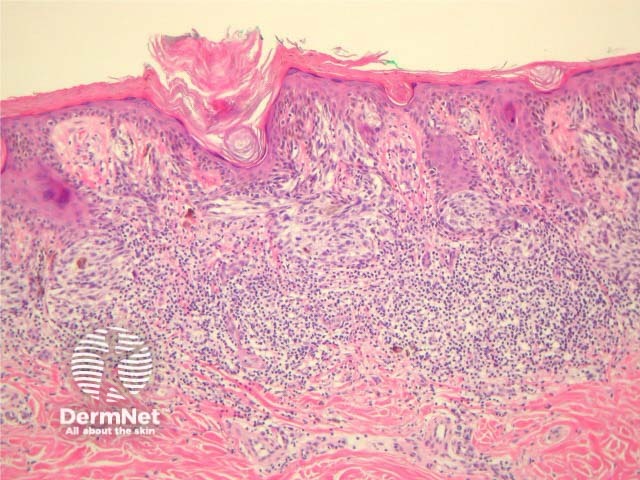

Most melanomas have an initial radial growth phase within the epidermis and sometimes within the papillary dermis (figure 1, 2), which may be followed by a vertical growth phase with deeper extension (figures 3, 4). The exception to this is nodular melanomas, which either skip the radial growth phase or the radial phase is rapidly overrun by the vertically growing tumour. It is also possible that they arise within dermal melanocytes. It has been proposed that lesions in the radial growth phase are incapable of metastasis, however there are numerous examples of thin melanomas that have behaved aggressively, even without convincing evidence of vertical growth.

Figure 1

Figure 2

Figure 3

Figure 4